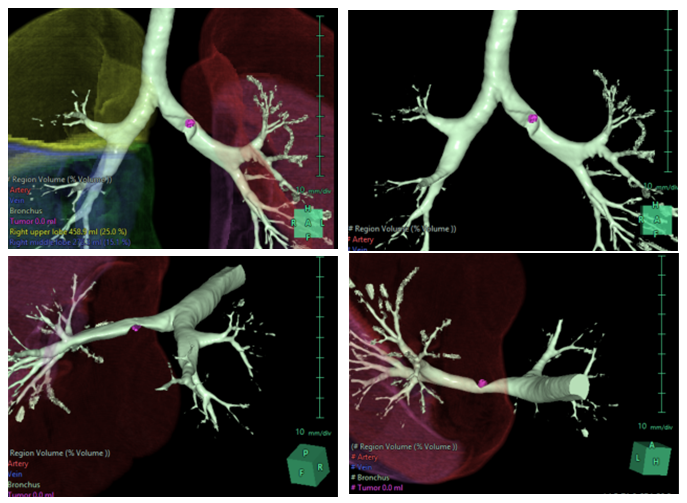

为保证手术顺利开展,胸外科团队进行了术前3D重建等详尽术前准备,并多次进行手术方案推演。

术前该病例气管三维重建图(图源:港大深圳医院胸外科)